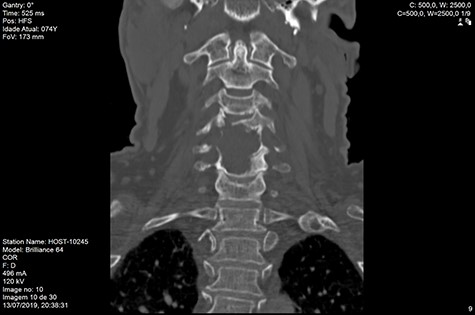

Computed tomography (CT) (Figs 1–3) and magnetic resonance imaging (MRI) (Figs 4–6) of the cervical spine were performed and revealed a lytic lesion involving most of C4, C5 and C6 vertebral bodies with bilateral extension to the posterior spinal elements of C4 and C5 and complete disruption of C4-C5 and C5-C6 intervertebral discs.

The Spinal Instability Neoplastic Score (SINS) [4, 6, 7] for assessing spinal instability from metastatic disease was used and the lesion was deemed unstable (SINS 13), with impending risk of increased neurological damage.

Findings from laboratory tests (serum protein electrophoresis) led to the diagnosis of MM. The patient was placed on a Philadelphia c-spine collar and underwent local 3D external-beam radiotherapy (20Gy in five fractions).